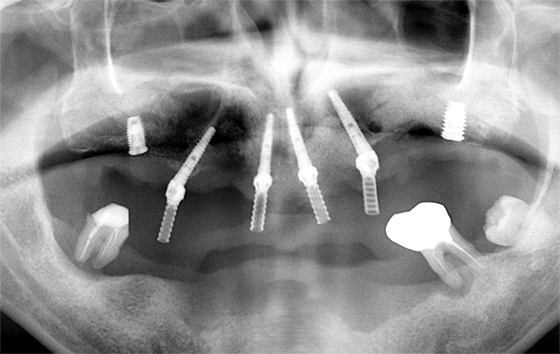

歯のレントゲン写真

現在、医療法の規制により、インプラントの埋入本数の実績を広告することは基本的に禁止されており、開示することは出来ません(誇大広告が多かったと言うことです)。

治療の成功率を左右する因子として、近年多くの論文が「術者の経験」を挙げるようになりました。

当院でインプラントを受けるメリットは、インプラント治療の累積量の多さに加え、10年、20年、30年前の治療の「その後」を診ている事だと感じています。

虫歯や歯周病により多くの歯を失った場合も、オールオン4により、片側の顎に最少4本のインプラントを埋入し、全ての人工歯をその上に固定することができます。

抜歯からインプラント埋入、仮歯の装着まで即日で行えるため、時間的、身体的な負担が少なくなるほか、片顎全ての歯を一気に治療することができ、経済的な負担も最小限に抑えて噛む力を取り戻すことが可能です。

骨の量が不足しているなどの理由でインプラント治療を断られてしまった方でも、骨造成を行うことでインプラント治療を受けられる可能性があります。

骨造成は、難易度が高く治療技術と経験が問われるため、実際に高い成功率を持って治療を行える歯科医師はごくわずかです。

当院は、中部地方の中核インプラント施設として、各地の歯科医療機関様よりご依頼を受けて、難しい骨造成症例の解決に力を入れています。